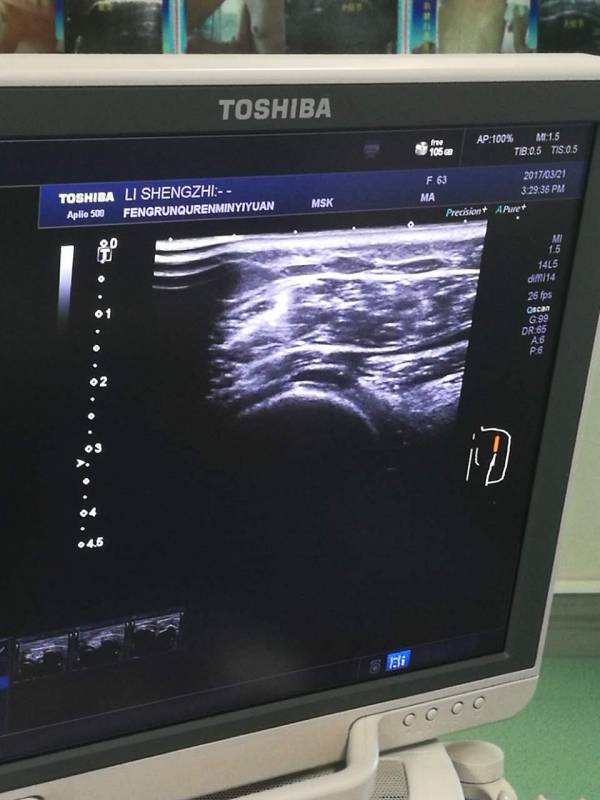

参观唐山市丰润区人民医院

全国肌骨超声培训基地

多科室,多专业,多学科,多专业的协助

传承,创新,规范,坚持

一定会取得巨大收获